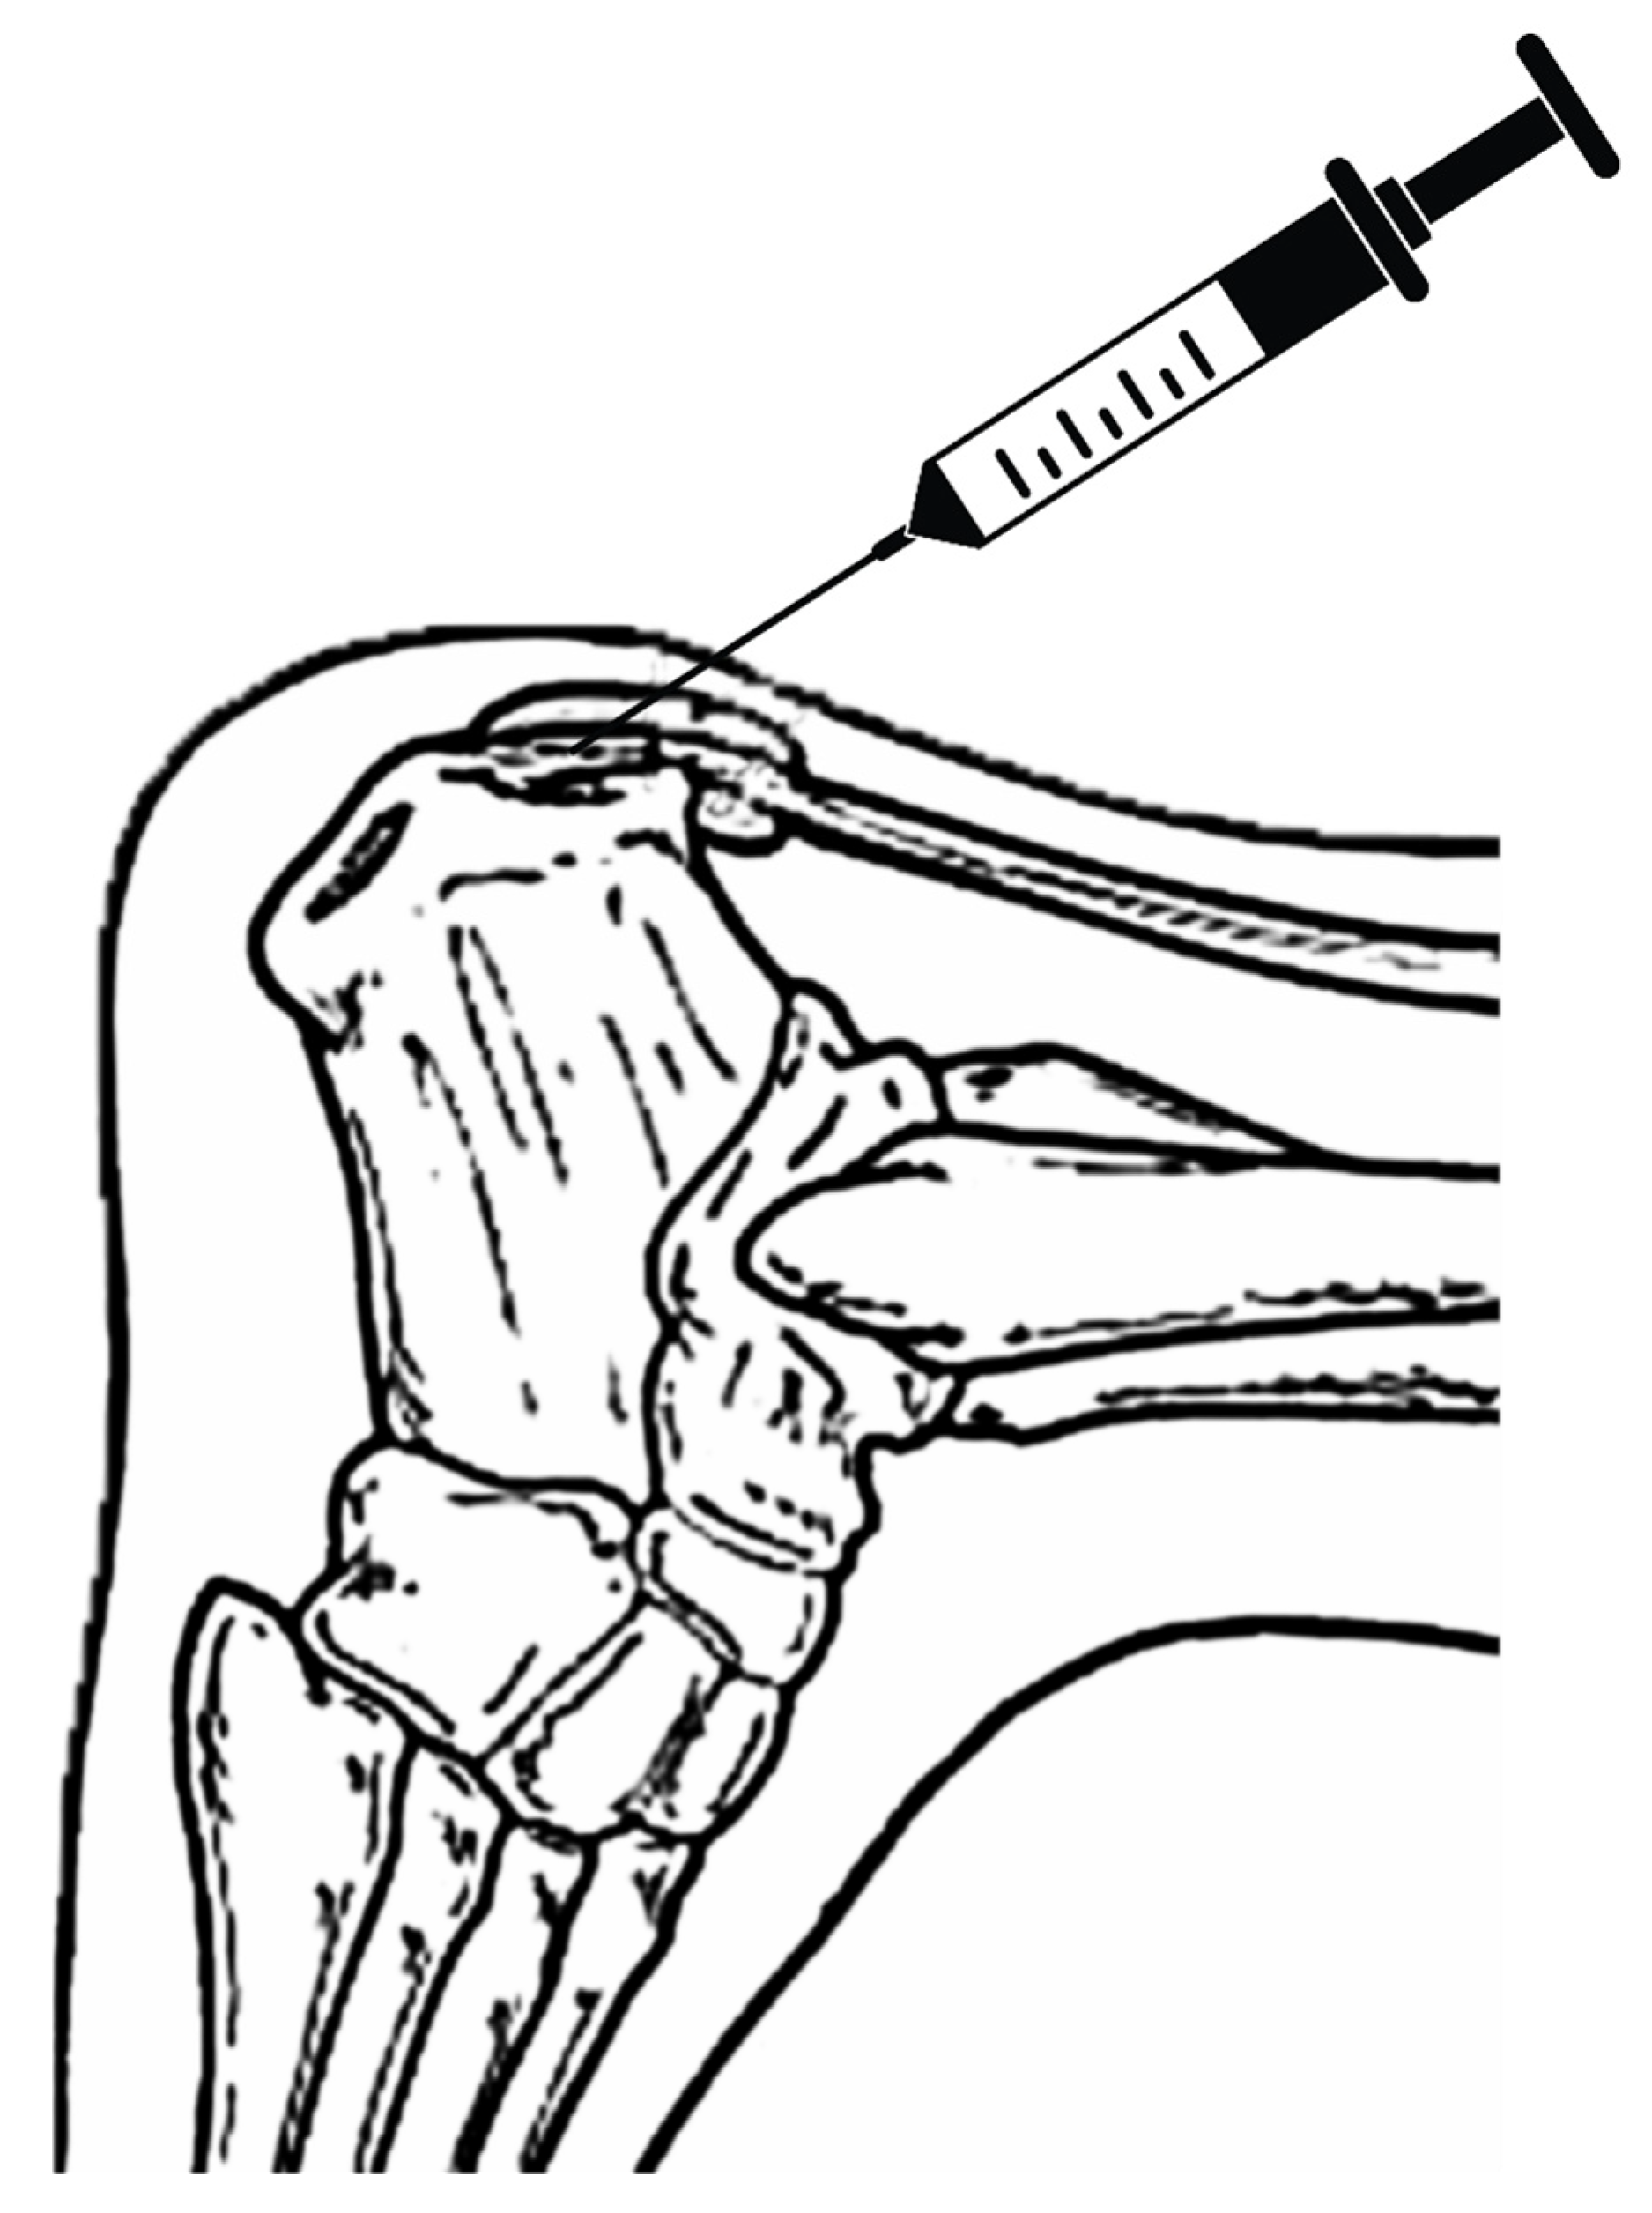

The procedure included the application of an umbilical cord tissue matrix, also known as Wharton’s Jelly, extracorporeal pulsed-activated therapy (EPAT), and class IV laser therapy. The patient was placed in the prone position without a tourniquet. It is essential to place the local anesthetic of choice more proximal away from the area to be treated. Lidocaine, 1% plain, was utilized to block the retrocalcaneal nerves, including the posterior tibial and sural nerves. The lower extremity was prepped and draped in the standard sterile technique. Prior to the application of the tissue allografts, the patient received EPAT at 11Hrtz, 1.4 bars, for 3521 pulses to the affected tissue. While the above EPAT was performed, 2ml of cryotext, a minimally manipulated tissue allograft, was thawed slowly per laboratory guidelines in a 35-degree bath. Under real-time ultrasound guidance using Esoate My Labs 15.0 MHz with a 4cm transducer head (Figure 3, Figure 4 and Figure 5), the Wharton’s jelly allograft was transplanted along the insertion (enthesis) in the frontal plane in a fanning-like technique as well as fanning in the sagittal plane. This application was accomplished just proximal within the intratendinous area beneath the paratenon around the tendon proper by strategic supplementation, as well as between the paratenon and circumferentially around the tendon proper. Further “needling” with a 22 gauge needle was performed to encourage neovascularization. The patient was instructed not to take NSAIDs or steroids and to refrain from high-impact activities. The patient was given acetaminophen to take as needed. The patient was scheduled for biweekly class IV laser treatments for the next three weeks to provide photobiomodulation. A pneumatic boot was fitted for two weeks.

Figure 3. Diagram of Wharton’s jelly application at the tendon insertion.